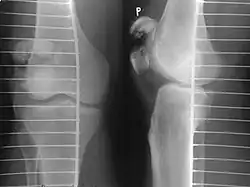

Vertical patella fracture

The patella can break in various ways depending on the way it is injured, and into two or more pieces.[1] Types include transverse, the most common, with one fracture line;[5] marginal; osteochondral; and the rare vertical type, or stellate, where a direct compression force gives rise to a comminuted pattern.[5][7] Patella fractures can be further classified as displaced, where the broken ends of bone do not line up correctly and separate by more than 2mm, or undisplaced and stable where pieces of bone remain in contact with each other.[1][7] If fragments of patella bone stick out from the skin it is known as an open patella fracture, and closed if the overlying skin is intact.[1]